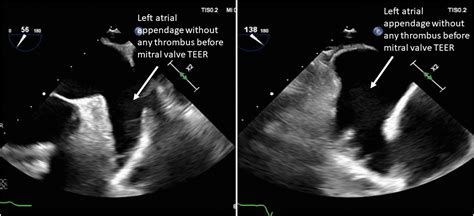

• tte vs tee Medical

• Tee vs Tte Procedure

• Tte Views

• TEE Test

• Tee with Cardioversion

• tte vs tee Imaging